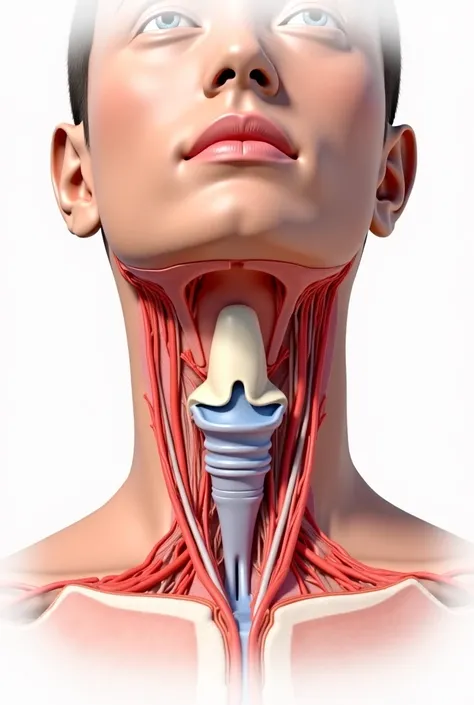

Pictures of swollen thyroid gland in neck, Use a Canon EOS 5D Mark IV with a 24

pictures of swollen thyroid gland in neck, Use a Canon EOS 5D Mark IV with a 24-70mm f/2.8 lens. Settings: ISO 100, aperture f/8, and shutter speed 1/125s to capture a sharp, vibrant image with a wide depth of field.

pictures of swollen thyroid gland in neck